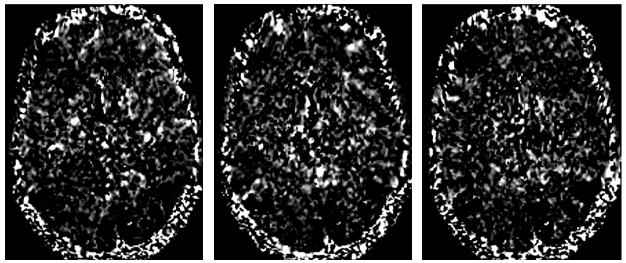

Refer to caption

Figure 1: Examples of a transverse section beta coefficient images for subject #1 in the NSD dataset. These volumes were acquired while watching samples 1, 6, and 8 (from left to right) of the test set. For each volume, the transverse section at voxel 80 was considered and values below the 40thsuperscript40𝑡40^{th}40 start_POSTSUPERSCRIPT italic_t italic_h end_POSTSUPERSCRIPT percentile and above the 95thsuperscript95𝑡95^{th}95 start_POSTSUPERSCRIPT italic_t italic_h end_POSTSUPERSCRIPT percentiles were saturated to pure black and white respectively.

The fMRI-stimulus pairs were obtained by the open-source Natural Scenes Dataset (NSD)  [1]. This comprised 7T fMRI recordings, along with BOLD signals, from eight healthy participants. During continuous acquisitions, they viewed natural color images, taken from the Common Objects in Context (COCO) dataset [15]. COCO images were 425×425 pixels and accompanied by a description in English natural language. The beta coefficients were computed using data in the NSD (Fig. 1), according to the methodology described in sec. 3.1) . In NSD, pre-defined ROIs were available for each subject, allowing to focus on relevant voxels and distinguish between low-level visual areas (such as V1, V2, V3, and V4) and higher-order visual areas involved in recognizing faces, places, words, and body parts within the inferior temporal cortex. Z-score normalization was applied to beta values, multiplying each sample by the mean and dividing by its standard deviation, both computed on the entire dataset. According to the literature [30, 21], 90% of the samples was used to build the training set, while the remaining 10% composed the test set. Out of the eight participants, just four (#1, #2, #5, and #7) were retained for this study because they underwent the full acquisition protocol. As an example, for subject #1, 37 acquisition sessions were performed, each acquisition involving 750 stimulus images (administration time 4 s). For each stimulus, the BOLD signal was acquired in that time frame. General model transform mapped the BOLD signal into the beta values. After applying the above-cited ROIs, 9,841 one-dimensional vectors of beta values were attained, each composed of 15,724 elements.